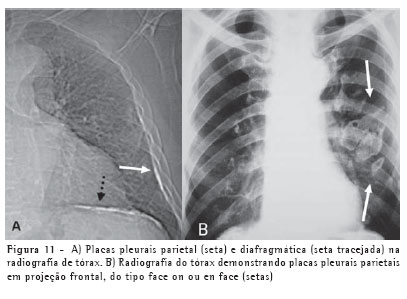

As placas pleurais são a manifestação mais comum da exposição ao asbesto, sendo consideradas marcadores de exposição. Envolvem mais comumente as porções posteriores e laterais da pleura da parede torácica, entre a sexta e a décima costelas, e a pleura diafragmática, principalmente na sua porção superior. A maior parte ocorre na ausência de asbestose e raramente detecta-se asbestose quando placas pleurais não estão presentes. A radiografia do tórax é até hoje o método de imagem mais utilizado na avaliação das placas pleurais (Figura 11).(8-9)